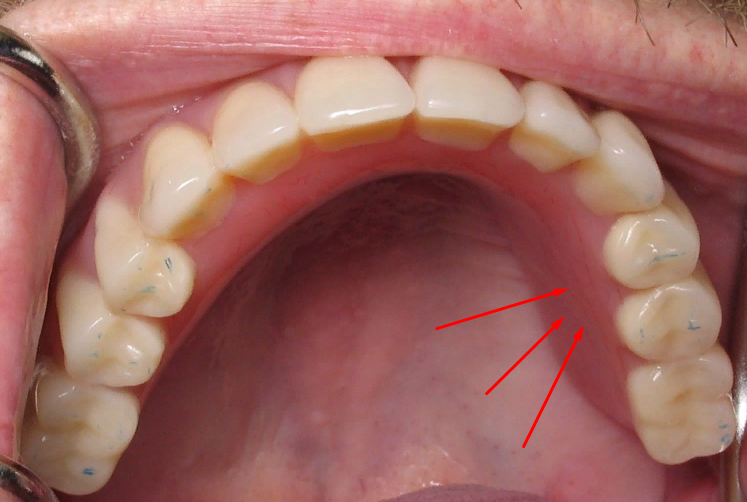

Здравствуйте, ситуация: болит десна. (фото с интернета, место указано стрелками) зуб мудрости вылез где-то на протяжении 2 недель, на 7 нарощенный зуб+ штифт, думала, что зуб мудрости двигает остальные зубы, но нет, места хватило, он стал нормально, даже зубная нить отлично проходит между зубами. А вот десна болит, при нажатии языком.